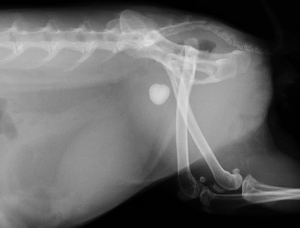

下の写真は膀胱結石が尿道結石となり尿路閉塞を生じた一連の変化をレントゲンで撮影したものです。数週間にわたる血尿と「排尿時のしぶり」と頻回尿を症状とする排尿障害を起こしていたウサギのものです。レントゲン検査では1cm程の膀胱結石が確認されました。

膀胱炎にやそれに伴う頻尿などの諸症状に対する対症療法を行ってもあまり症状の改善がみられないため、手術を計画しましたが、その前に排尿困難に陥って緊急で来院した際のレントゲン写真が下の二枚です。膀胱内にあった結石が尿道結石となり急性の尿路閉塞を生じています。

このように上流でつくられた結石が下流へ流れ、そこで急性の尿路閉塞を生じるということが、尿路結石症の最も激しい症状を引き起こします。尿路閉塞に対しては結石の閉塞状態をはじめ、腎機能の評価をはじめとする全身の評価と緊急手術を含めた閉塞解除に関わる治療を並行して迅速に行わなければなりません。

上写真のウサギは緊急の尿道切開術によって尿道結石の摘出を実施いたしました。